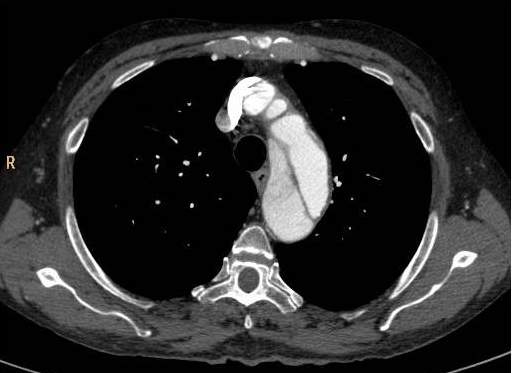

There are two main types of aorta dissection according to the Stanford classification: type “A” when the ascending aorta is involved, and type “B” when the dissection occurs distal to the origin of the left subclavian artery and it does not propagate to the level of ascending aorta or the aortic arch. The two types are distinguished because of their acute complications: type “A” dissection can cause the obstruction of the coronary trunks or, in case of a pericardial rupture, it can cause consequent pericardial tamponade and sudden death. Hence these cases require immediate surgical intervention with a cardiac surgical background. In contrary type “B” dissection can cause the acute obstruction of the abdominal aortic branches and can lead to life threatening conditions only in a subacute manner (intestinal ischemia, renal insufficiency). These conditions can also require surgical intervention (vascular surgery) but they rarely need immediate surgery. Both dissection types have the late stage complication of the development of aneurysm that occurs due to the weakened and constantly expanding vessel wall, which constitutes a growing risk for aortic rupture.

Primary diagnostic imaging is usually performed as an emergency examination, patients are often unstable, or gravely ill and in poor condition. Therefore, CTA is a most advantageous method; it can provide a diagnostic quality imaging even on a non-cooperative patient with. It is crucial to determine the type of dissection (A or B-), the involvement of the supraaortic and abdominal branches, the origin of the side branches, and the anatomy of the false and the real lumen and their permeability. A highly pulsating aortic root can cause diagnostic problems because of the vessel movement. The artifact caused by the moving arterial wall can mimic an intimal-flap, especially at the root of the ascending aorta. However, this can be avoided with ECG gated examination; hence patients with symptoms of acute coronary syndrome should be directed to a centum where ECG gated imaging is available.

Image

The lumen is divided by the detached intimal layer that can be followed from the origin of the left subclavian artery to the descending aorta.

The real lumen shows a fast filling and a more intense contrast enhancement,

while the false lumen shows a less intense contrast enhancement due to its decreased flow.

Fig. 26., 27., 28.: Type B aortic dissection CT angiography